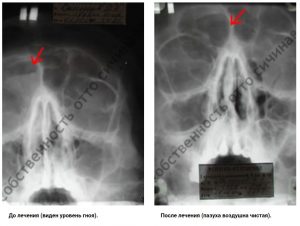

Хронический фронтит – это гнойно воспалительное заболевание лобных пазух. Обострение которого чревато развитием заболеванием головного мозга. Не редко такие обострения могу привести к летальному исходу.

Традиционный процесс лечения фронтит происходит следующем способом – введением через нос в лобную пазуху вводится канюля с помощью которой происходит промывание пазухи. Однако, кроме такого метода, в традиционной медицине прибегают так же к другой, более жесткой методике, лечения в виде трепанопункции лобной пазухи. Над надбровной дугой осуществляется небольшой надрез кожи, а затем костную ткань засверливают с целью создания отверстия для установки пластиковой трубочки, через которую промывают пазуху. Как правило, таким пациентам внутривенно капельно вводят антибиотики в сочетания с гормональными средствами

В нашей клинике такие методики считаются варварскими. Так-как есть методики лечения без операций, которую как правило, не применяют в классической медицине.

В нашей клиники метод лечения хронического фронтита отличается естественными физиологическими процедурами:

Таким образом нам удалось вылечить несколько тысяч больных обреченных на хирургическое вмешательство, чему в подтверждения представлены видео отзывы нашим пациентов.